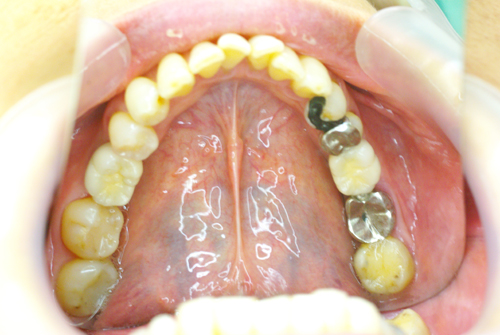

インプラント治療完了

白くきれいな歯が入りました。周りの歯も白くしました。残りの銀歯も順次、白いきれいな歯に入れなおしていきます。